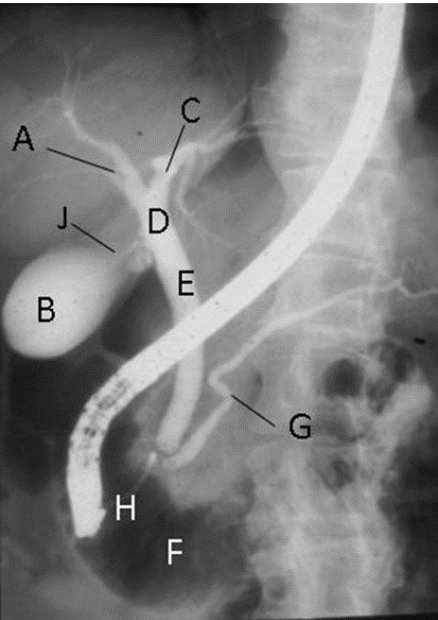

What contrast procedure was performed to produce this image?

Identify A – H:

ERCP – Endoscopic Retrograde Cholangiopancreatography

A-Right Hepatic Duct

B-Gallbladder

C-Left Hepatic Duct

D-Common Hepatic Duct

E-Common Bile Duct (CBD)

F-Duodenum

G-Pancreatic Duct (Duct of Wirsung)

H-Ampulla of Vater (Hepatopancreatic Ampulla)

1)procedure performed?

2)contrast media used?

3)How contrast media administered?

1)ERCP – Endoscopic Retrograde Cholangiopancreatography

2)Water-Soluble Iodinated

3)retrograde (tube through mouth→ampulla of vater then backwardly injected in bile duct)